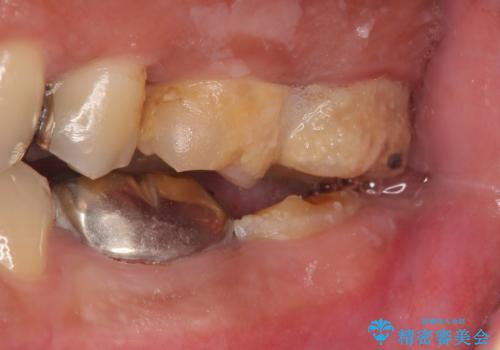

- 左下7の歯しみる、被せ物を被せてもすぐに外れてしまうといらっしゃった方の症例です。

左下に被せ物を被せるクリアランス(補綴のための上下のスペース)ないため、十分な歯冠長を確保するため歯冠長延長術を行いました。

その後歯肉の回復を待ち、フルジルコニアクラウンにて補綴を行いました。